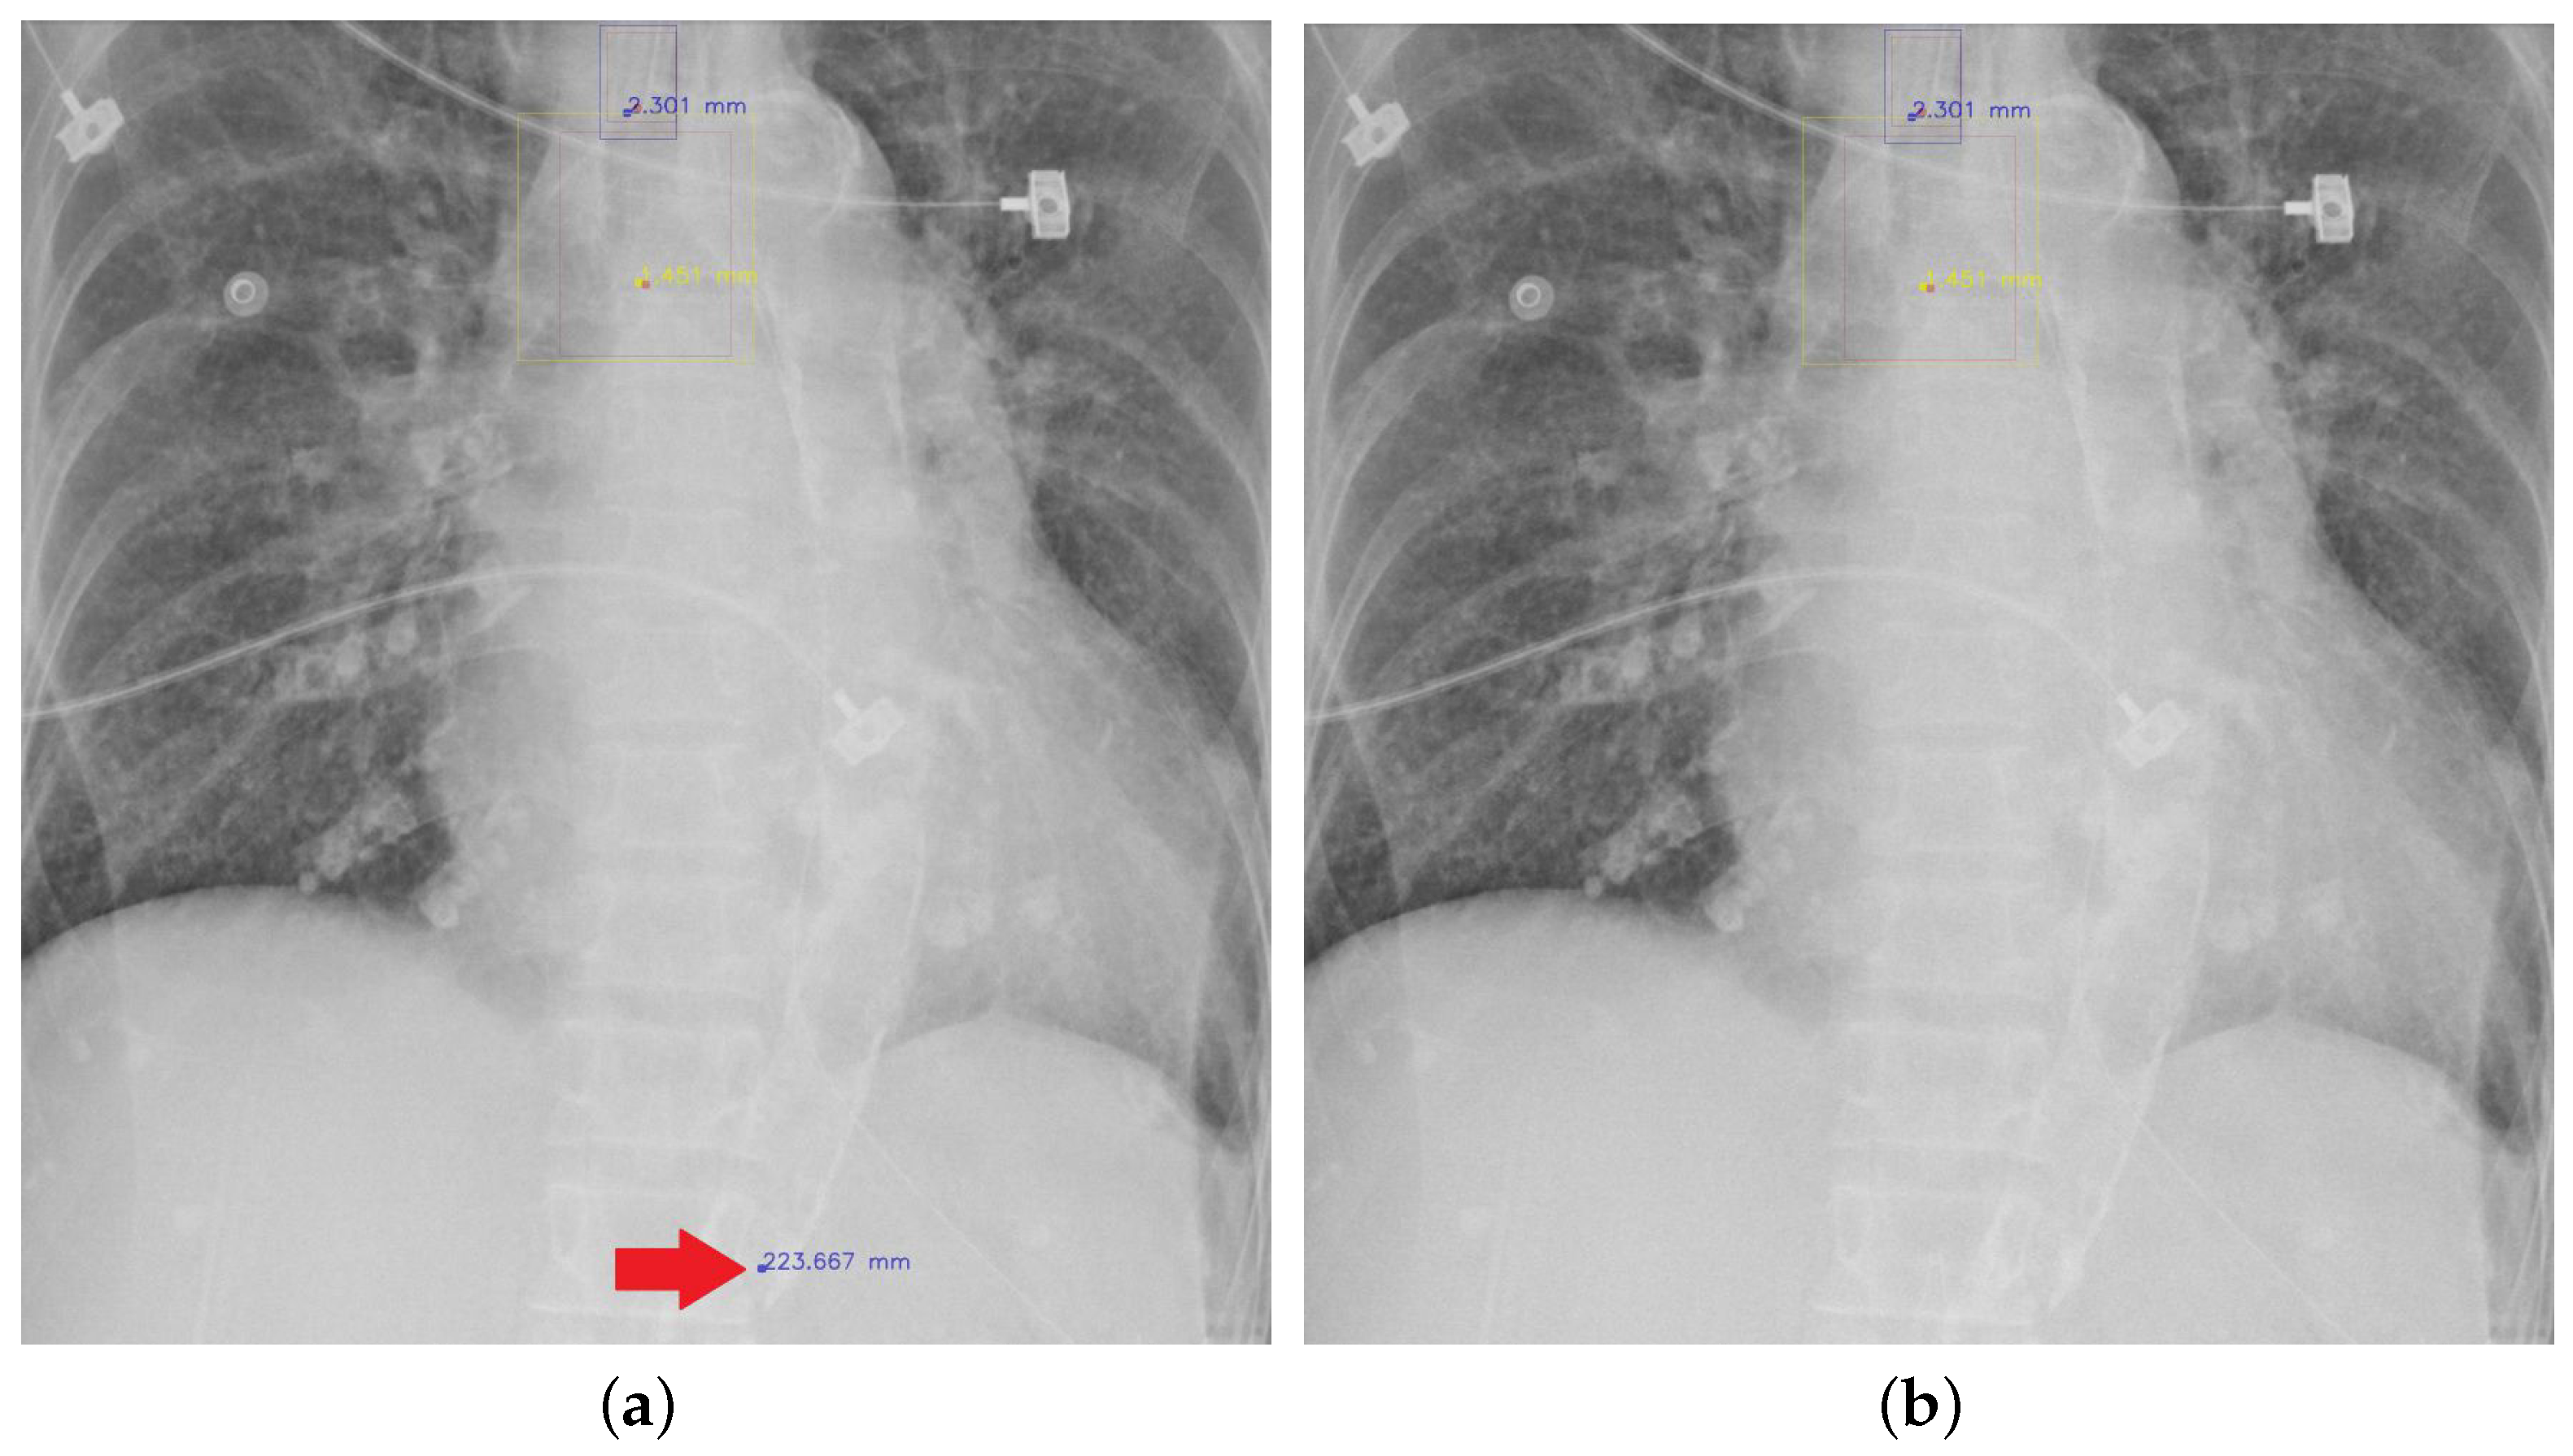

Determining Carina and Clavicular DistanceDependent Positioning of Endo Tip Carina In this position, there is a risk of overventilation of the right lung and underventilation of the left. The tip of the endotracheal tube should be about 5 cm from carina or roughly halfway between the clavicles and the carina. The tip of the endotracheal tube should be about 5 cm from carina or roughly halfway between the clavicles and. Endo Tip Carina.

From www.mdpi.com

Diagnostics Free FullText Detecting Endotracheal Tube and Carina Endo Tip Carina In this position, there is a risk of overventilation of the right lung and underventilation of the left. In this example, the tip of the ett (yellow arrow) is too close to the carina (orange arrow), and is at the origin of the right main bronchus. This is because the tip may travel up to 2 cm. A malpositioned endotracheal. Endo Tip Carina.